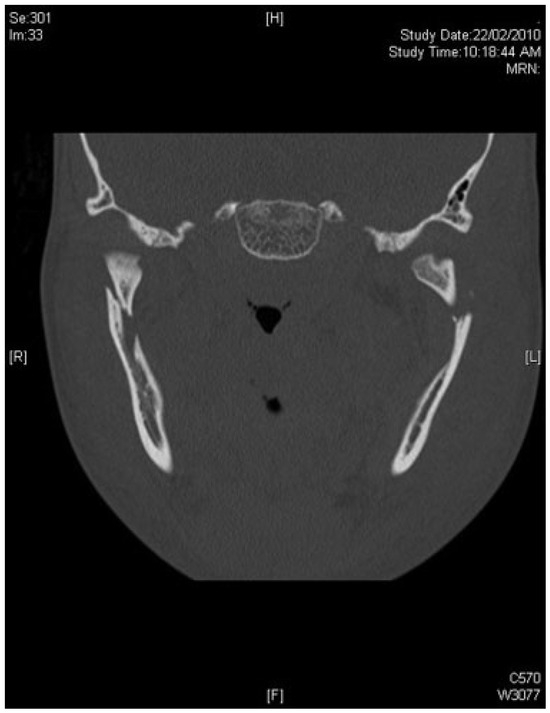

A 16-year-old Caucasian adolescent was the driver of a car that collided with a tree. He presented one day later with progressive bilateral facial pain and swelling. Examination noted an anterior open bite and bilateral preauricular swelling, worse on the left than the right (Figure 1). Computed tomographic (CT) scans of the face showed bilateral mandible subcondylar fractures associated with a minimally displaced symphyseal fracture (Figure 2). Two days after the accident, it was observed that the swelling on the left side had increased noticeably; this was attributed to fracture hematoma. The patient underwent an elective operative reduction and internal fixation of the mandible fractures the following day. A lower buccal sulcus approach was used for exposure of the symphyseal fracture, and rigid fixation was achieved with a six-hole 2.0-mm locking titanium plate (Matrix Mandible, Synthes, West Chester, PA). The right subcondyle fracture was fixed through a preauricular approach with a five-hole 1.5-mm plate.

Figure 2. Coronal view of computed tomographic (CT) scan of the patient showing bilateral mandible subcondylar fractures.